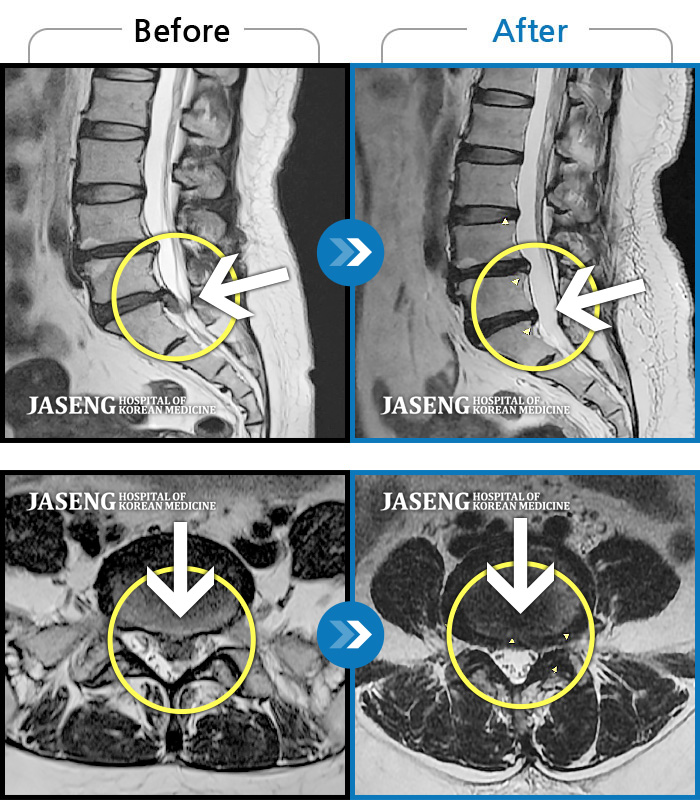

허리디스크

해운대 · 김상돈 원장

허리가 찌릿찌릿하고 찢어질 것 같은 통증

촬영시기

2024.01.08 ~ 2025.08.12

2025.08.29